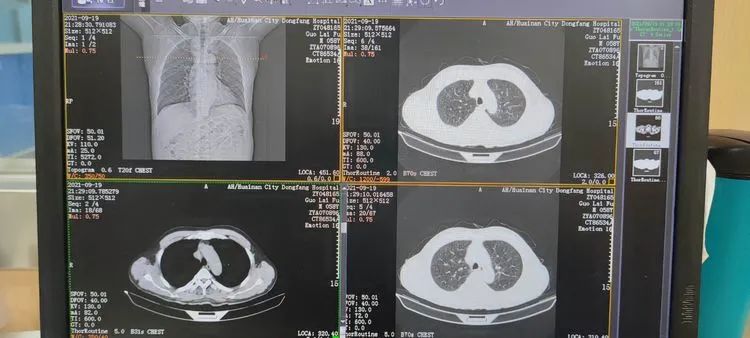

检查结束后,在科室人员的指引下无需等待胶片打印,可以直接前去门诊专家处读片,在门诊专家的电脑上可以清晰的看到该患者的影像图片,帮助专家作出更明确的诊断。这正是李郢孜医院影像科启用电子胶片的便利之处。

而所谓电子胶片便是将传统塑料胶片的一种信息化升级,是一种基于移动互联和云储存为支撑的新型的医学影像服务。它能将患者拍摄的医学影像上传至云服务器中,方便医生和患者随时随地通过手机、iPad和PC端访问云端进行查阅。

该名就诊患者居住在孤堆孙老郢村,前来李郢孜医院路途遥远,在李郢孜医院启用电子胶片之后,便不用再来回跑路折腾,只需在家手机扫描检查登记时给予的二维码,图像及报告便能在手机查看了。

李郢孜医院在东方医院集团领导的关心和支持下,通过互联网平台,开展云影像服务,在李郢孜医院影像科做的检查图像直接上传云端,由东方医院集团总院云影像中心阅片诊断,让患者在集团下属基层医院就诊也能享受总院专家的诊疗服务。